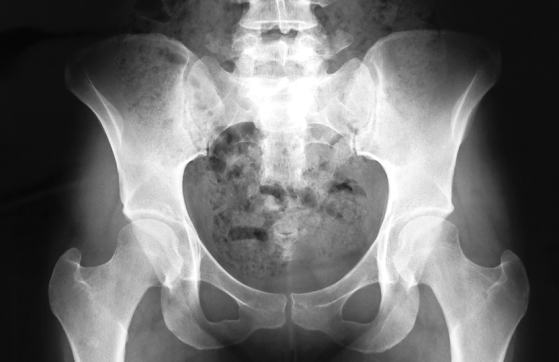

骨盤の写真をみてみましょう。骨と骨の間の適切な「すきま」が見えますか?この適切なすきまこそ、「骨盤のあそび」を作ってくれる基礎です。そして、この「骨盤のあそび」は、すきまがありすぎても、なさすぎてもボディメイクするには良くありません。現実にはすきまがありすぎという女性よりも、すきまが無さすぎで骨盤回りがガチガチに固まっている女性が以外に多いものです。